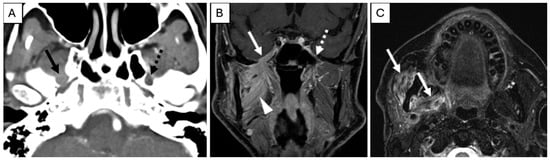

- Overfield, C.J.; Rhyner, P.A.; Hall, M.R.; Bhatt, A.A. More than Skin Deep: Imaging of Dermatologic Disease in the Head and Neck. RadioGraphics 2024, 44, e240052. [Google Scholar] [CrossRef] [PubMed]

- Agarwal, M.; Wangaryattawanich, P.; Rath, T.J. Perineural Tumor Spread in Head and Neck Malignancies. Semin. Roentgenol. 2019, 54, 258–275. [Google Scholar] [CrossRef]